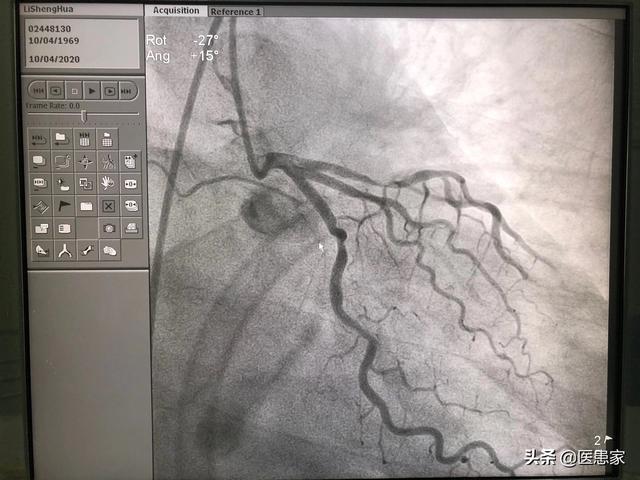

En ce qui concerne la sténose seule, une sténose coronaire ne dépassant pas 40 % est optimiste, du moins à court terme, sans trop d'anomalies ou de dangers, mais nous ne pouvons pas nous contenter de regarder le présent, et nous devons également tenir compte de l'évolution ultérieure.

Tout d'abord, plusieurs gros vaisseaux de l'artère coronaire ont une sténose qui atteint 50 %, c'est une maladie coronarienne ; une sténose <50 % appartient au moins à l'athérosclérose de l'artère coronaire, il y a une possibilité d'évolution vers une maladie coronarienne, il faut aussi la contrôler activement. Sténose de l'artère coronaire à 40 %, la plupart du temps la combinaison de l'hypertension, du diabète sucré, de l'hyperlipidémie et d'autres maladies sous-jacentes, cette fois-ci doit être activement contrôlée par des médicaments pour la tension artérielle, les lipides sanguins et la glycémie.

Cette sténose coronaire de 40 %, bien que dans la plupart des cas elle n'affecte pas temporairement l'irrigation sanguine des artères coronaires, peut, en cas de tabagisme, de fatigue extrême, etc., entraîner un spasme coronaire, une rupture de plaque, un angor et même un infarctus du myocarde, ce qui n'est pas sans poser de problèmes. Et si les facteurs de risque tels que les trois précédents ne sont pas activement contrôlés, l'athérosclérose coronarienne progressera et finira par devenir une véritable maladie coronarienne.

Les artères par lesquelles le cœur alimente son propre sang sont appelées artères coronaires. Il existe un critère pour ce que nous appelons habituellement la maladie coronarienne, à savoir un rétrécissement des artères coronaires supérieur à 50 %. Lorsque le rétrécissement des artères coronaires est inférieur à 50 %, on parle d'athérosclérose coronaire.